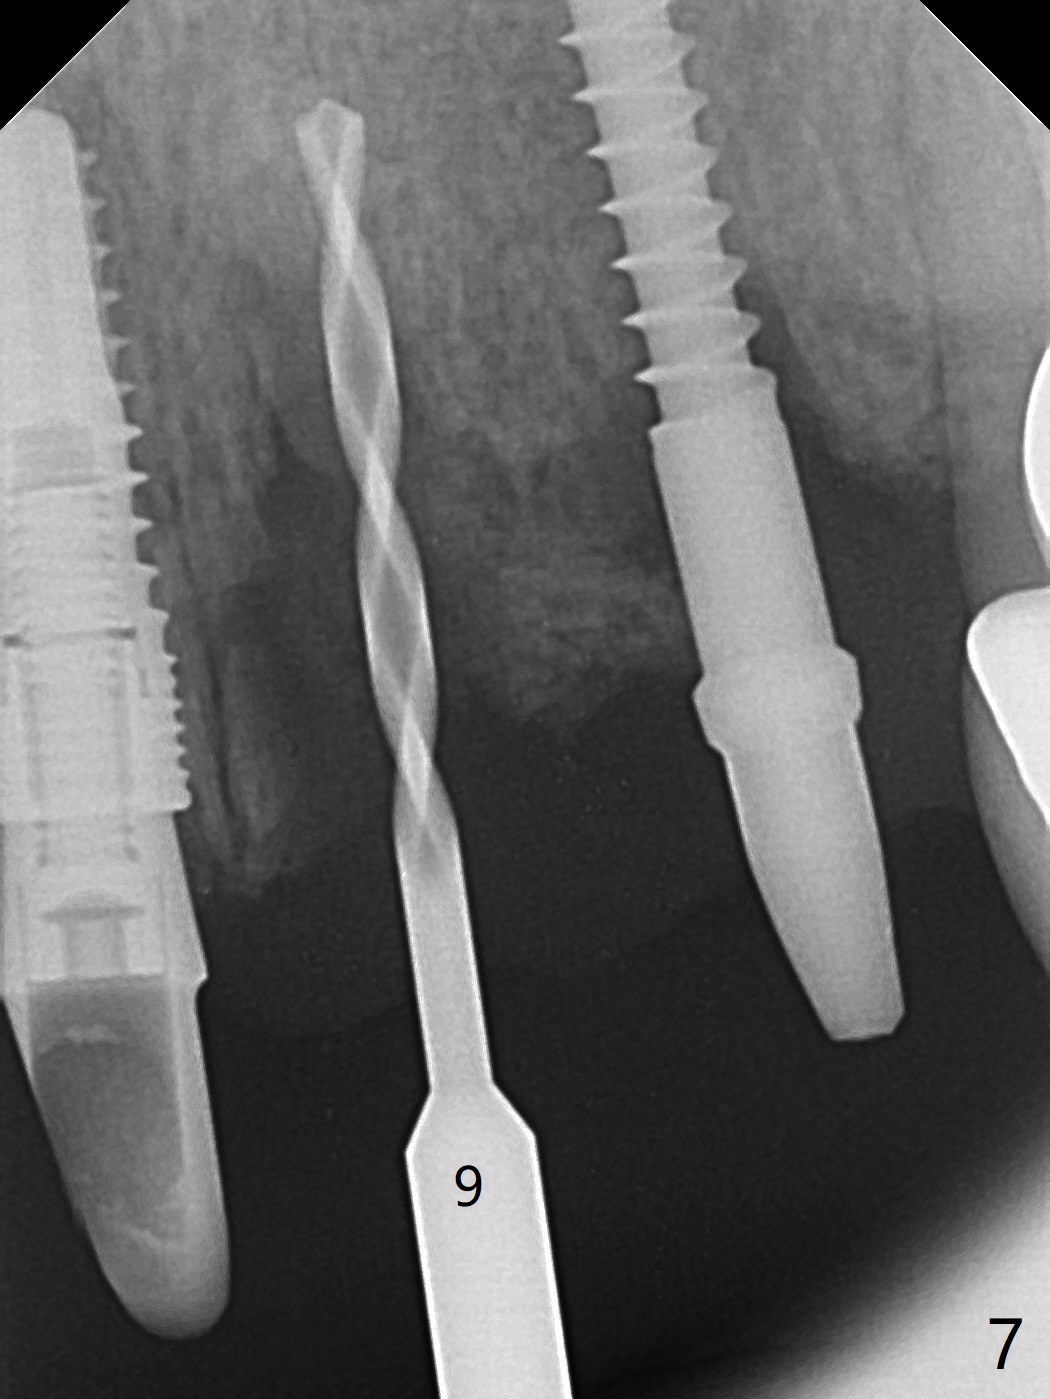

Incision shows exposure of microthreads at #9 and major threads at #10 due to buccal placement (Fig.1). There is bone palatal to the implant at #10 (Fig.2 P), to which a new implant will move. After implant removal, a narrower 1-piece implant (2.5x14(4) mm) is placed palatally at #10 (Fig.3,4) in combination of guide and free hand. At the site of #9 after implant removal, the guide is not used; a 3x17 mm angled 1-piece implant is placed with bad trajectory (Fig.5,6). After re-adjustment (Fig.7), the implant is placed at the right orientation (Fig.8). It appears that the guide is helpful. Allograft is placed mainly buccally (Fig.9,10 *), followed by a piece of collagen membrane (Fig.11). After tension release, flaps are approximated (Fig.12). The buccal gingiva at #9 and 10 recede nearly 2 months postop (Fig.13). Less recession at #9 is associated with more inflammation (Fig.14). The margin of the provisional is adjusted for gingival margin down growth and easy self cleaning with Water Pik (Fig.15). One month later, the gingival inflammation reduces, while there is no obvious buccal collapse (Fig.16,17). Impression is taken after laser gingivectomy nearly 4 months postop (Fig.18). While the gingiva around the implant at #9 is inflamed (periimplantitis?), the gingival cuff at #10 is well formed 5.5 months postop immediately before cementation (Fig.19). The buccal concavity at #10 is minimal (Fig.20). The gingival inflammation at #9 will be hopefully resolved after cementation of the final restorations (Fig.21). There appears to be new bone formation around the coronal implant threads 5.5 months postop (immediately post cementation, Fig.22). The microthreads at #9 may be not covered by the bone, the reason for the gingival erythema. The redness at #10 is asymptomatic 5.5 months post cementation (Fig.23). 粘固后两年牙槽嵴骨质并没有再生(图二十四),说明第一术中植体必须植入骨下(基台部分要长,否则难于修复),第二牙槽嵴处不应该有压力,植入2.5毫米植体,最后钻头应该是2.5毫米,骨下1-3毫米(尝试项目)。